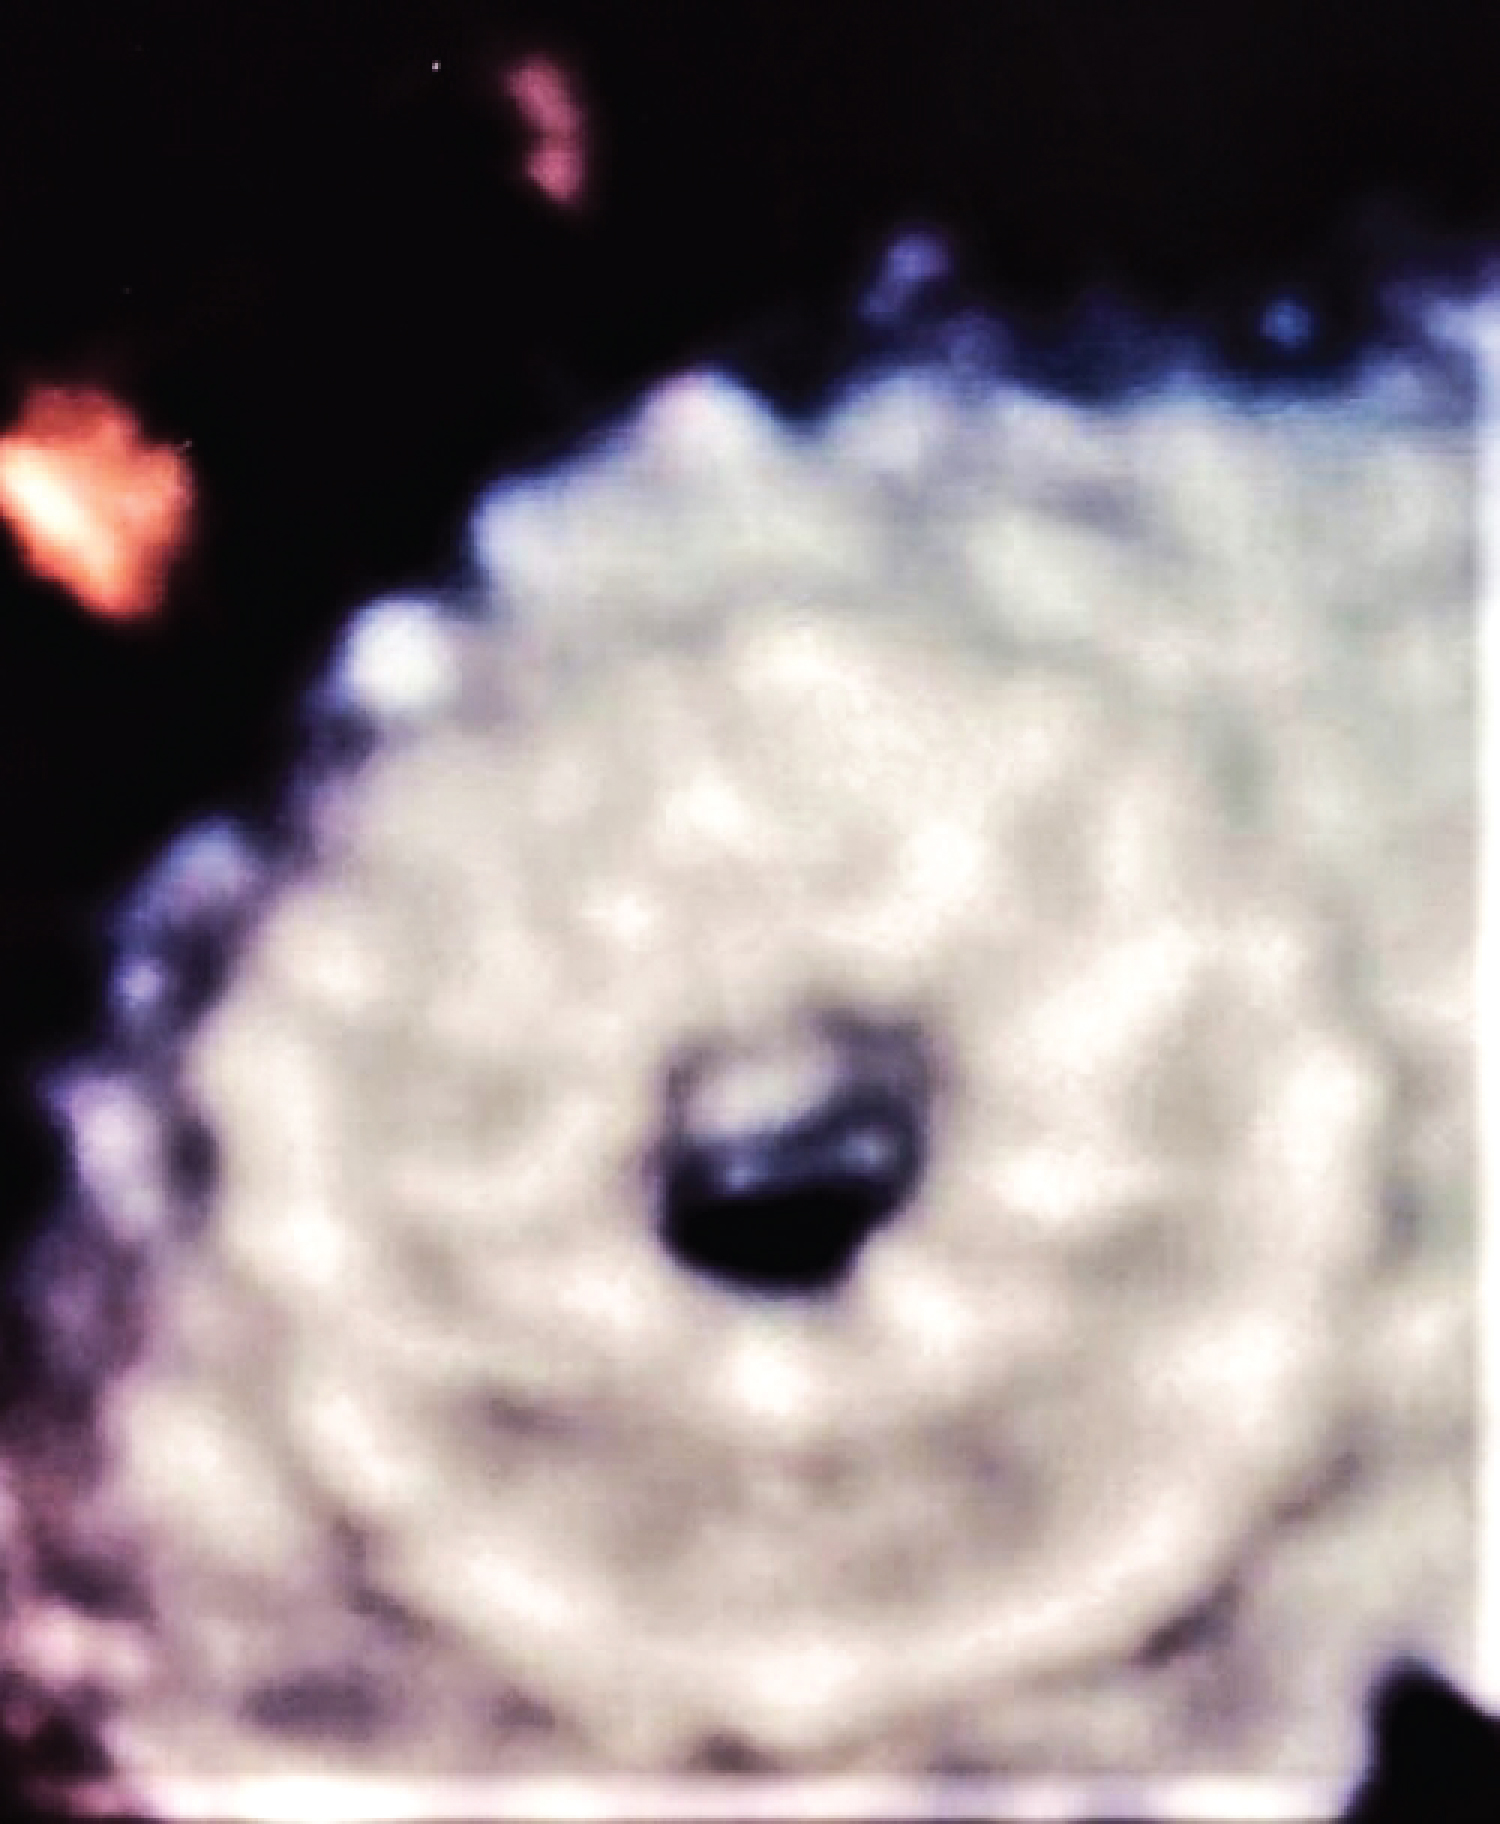

A 55-year-old man, hypertensive with type 2 insulin-dependent diabetes mellitus, dyslipidaemia and obesity (BMI: 33.96 kg/m2) underwent clinical evaluation because of more-than-3-month effort dyspnoea (NYHA III). His past medical history consisted of prior anterior ST-elevation myocardial infarction (STEMI) treated by percutaneous coronary intervention (PCI) with drug-eluting stent (DES) implantation on the left descending artery (LDA) and on the posterolateral artery (PLA). At follow-up, both DES resulted occluded while another PCI with DES implantation was performed on the obtuse marginal artery (OM1) due to a symptomatic critical CAD. A subsequent stress cardiac magnetic resonance (CMR) showed a moderate LV dysfunction (LVEF 40%) without viability of the left ventricular apex and the anterior wall. The patient was on optimal medical therapy including beta-blockers, ARNI, SGLT-2 inhibitor, diuretic, mineralocorticoid receptor antagonist). According to the recent 2021 ESC Guidelines on HF, the patient was diagnosed with advanced heart failure [1]: he presented typical symptoms of HF with persisting high N-terminal prohormone of Brain Natriuretic Peptide (NT-proBNP) and evident cardiac structural abnormalities; moreover, he had 4 episodes of pulmonary congestion requiring hospitalization, the last registered 6 months before, and developed a severe inability even to low-grade exercise. Due to this clinical scenario, the patient was admitted to our Cardiology Unit. Baseline trans-thoracic echocardiography confirmed left ventricle systolic impairment (LVEF 40%), but showed no right heart dysfunction nor severe pulmonary hypertension (e.g. pulmonary artery systolic pressure - PASP - ≥ 60 mmHg). Estimated ultrasonographic LAP at rest was 26 mmHg. Coronary angiography confirmed an occlusive in-stent restenosis on the LAD and a critical stenosis in the right coronary artery treated by DES implantation. Right heart catheterization reported mild pulmonary hypertension (PASP: 32 mmHg, diastolic pulmonary artery pressure - PAP: 24 mmHg, mean PAP: 27 mmHg) and increased PCWP at rest which was 20 mmHg. Based on these data the patient was considered a candidate for IAST using an 8-mm-diameter Atrial Flow Regulator device (Occlutech™). The procedure was successfully performed under general anaesthesia, through a hybrid fluoroscopic and transoesophageal echocardiographic guide. Procedural steps are described by Paitazoglou C, et al. [12] and are summarized in Figure 1. No complications were reported and the LAP has been acutely reduced following the generation of an iatrogenic inter-atrial shunt (final Qp/Qs 1.2) (Figure 2 and Figure 3). Patient was discharged 2 days after the procedures on dual antiplatelet therapy in association with beta-blocker, ARNI, diuretic, mineralocorticoid receptor antagonist, SGLT-2 inhibitor.

Figure 1: Procedural steps of AFR implantation. Panel A: positioning of a stiff wire in the left superior pulmonary vein; Panel B: atrial septostomy and septal dilatation (part 1); Panel C: septal dilatation (part 2); Panel D: crossing of the AFR delivery system through the septostomy inside the left atrium; Panel E: Advancement of the AFR delivery system inside the left atrium; Panel F: AFR initial release; Panel G: AFR traction test before complete release; Panel H: AFR complete release. AFR: Atrial Flow Regulator. View Figure 1